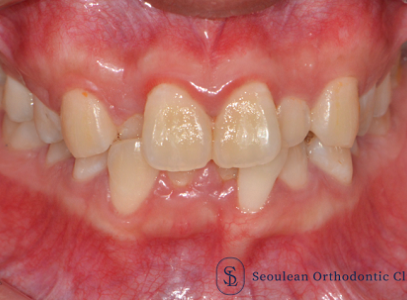

상·하악 중심선 비대칭과 2급·3급 구치관계, 비발치 교정으로 1급 교합 회복한 20대 여성 사례